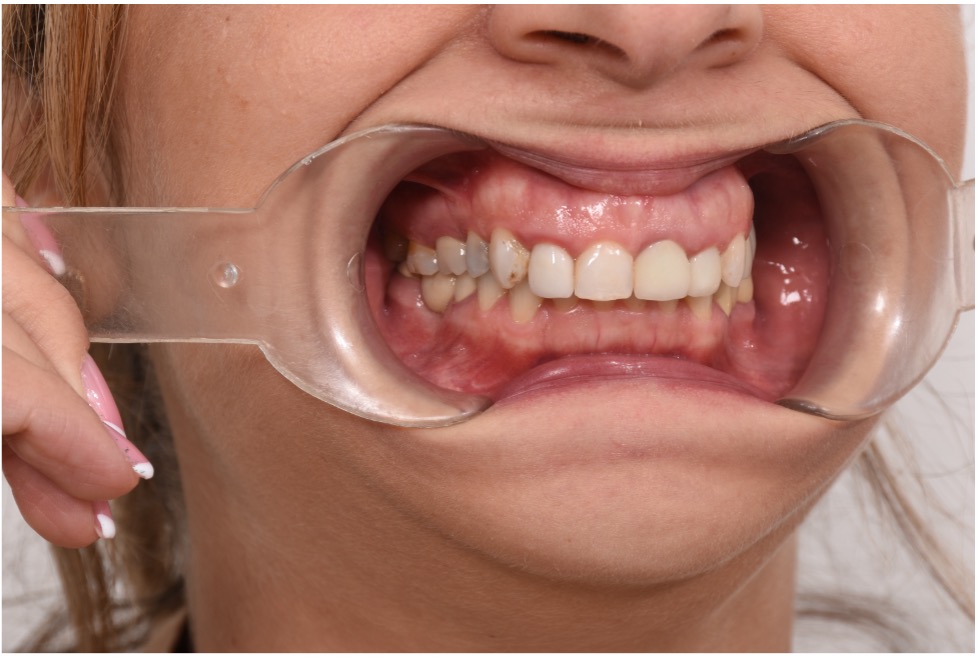

• Chief Complaint: Gummy Smile and Old Crowns

• Initial Diagnosis: Excessive Gummy Smile and Discolored old crowns

Step 1: Diagnostic Assessment and Smile Design The treatment began with a comprehensive evaluation of the patient’s smile using facially guided diagnostics. The Facial Flow Concept was employed to assess the relationship between the patient's facial structure, lips, smile arc, and gingival display. SmileFy software was utilized to generate a 2D digital smile simulation.

This visualization allowed both the clinical team and the patient to preview the planned esthetic outcome. It also provided a platform for mutual understanding and expectation management, forming a blueprint for all subsequent steps.